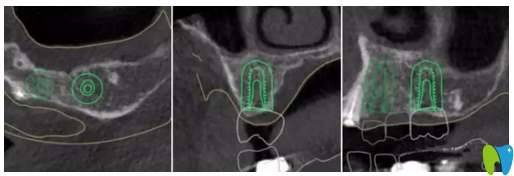

▲ 患者左上6牙位模擬種植圖

應(yīng)患者要求,并考慮到患者自身因素(高齡、高血糖及高血壓史),本著拜博口腔精 準(zhǔn)種牙的原則,擬定出數(shù)字化導(dǎo)板種植合并傳統(tǒng)修復(fù)的治療方案:

① 一期16,17,24,26數(shù)字化全程導(dǎo)板引導(dǎo)種植,二期16,17單冠修復(fù),24,25,26連橋修復(fù)。